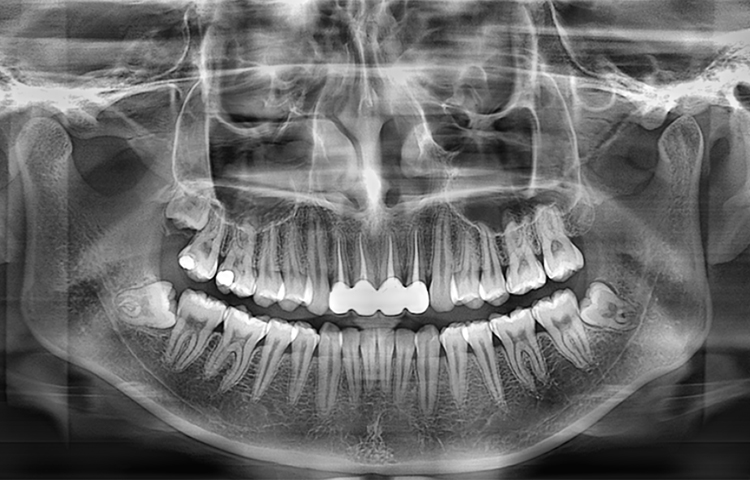

Панорамный аппарат Meyer обеспечивает стоматологов высококачественными панорамными и цефалометрическими снимками, который может быть использован для диагностики всего зубного ряда, нижней челюсти и ВНЧС. Он также подходит для оценки челюстно-лицевых переломов и разработки планов ортодонтического лечения.

Скриншоты снимков